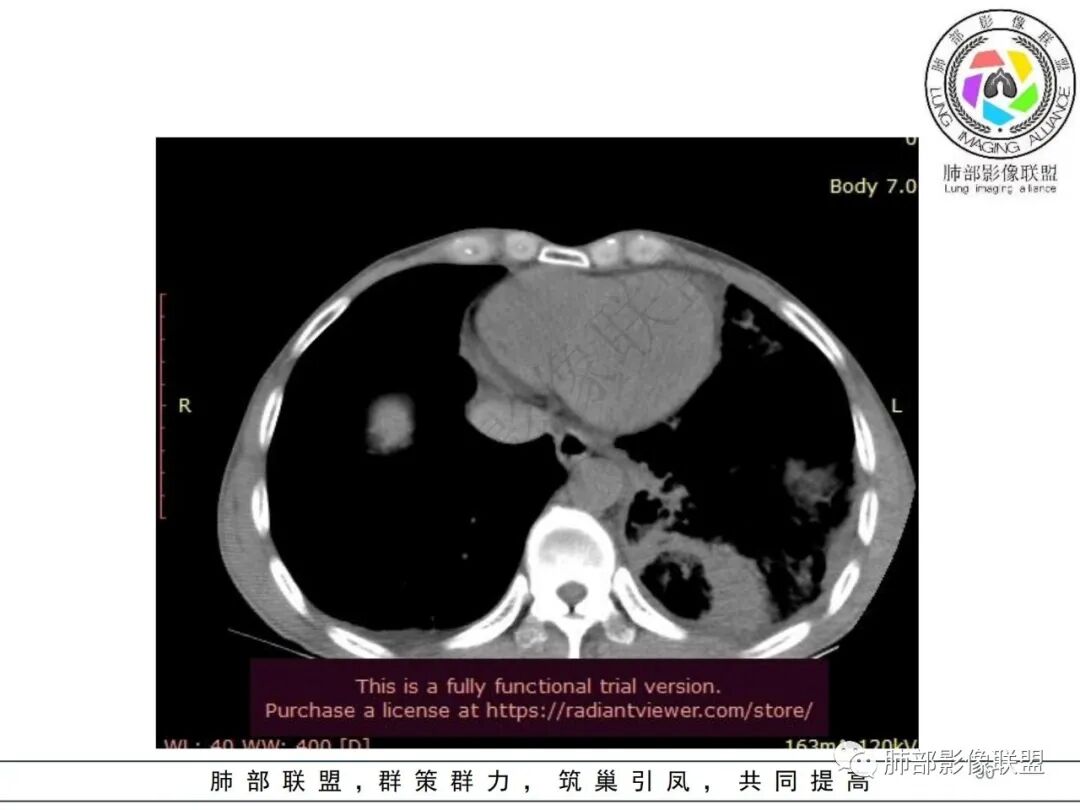

影像表现:双肺多发结节、实变影,大部分病灶边界不清,随机分布趋势,左下肺“反晕征”,似有形成空洞趋势。左侧胸腔积液。治疗后复查 ,大部分病灶吸收好转,呈较为典型血播分布,肝脏低密度块影,边界不清,符合肝脓肿。

综合分析:结合症状及实验室检查,均提示本例为感染性病变;海南居住史首先会让我们考虑是否为类鼻疽,类鼻疽主要为血道播散,此时判断病灶为气道还是血道有重要鉴别意义。首次检查片分析气道、血道均有,没有薄壁气囊,结合临床PCT等实验室检查,肺炎克雷伯杆菌感染的可能性增大。复查片显示肝脓肿,加之糖尿病,临床诊断趋于明朗化。血培养及痰培养均可见肺克雷伯杆菌,诊断明确!